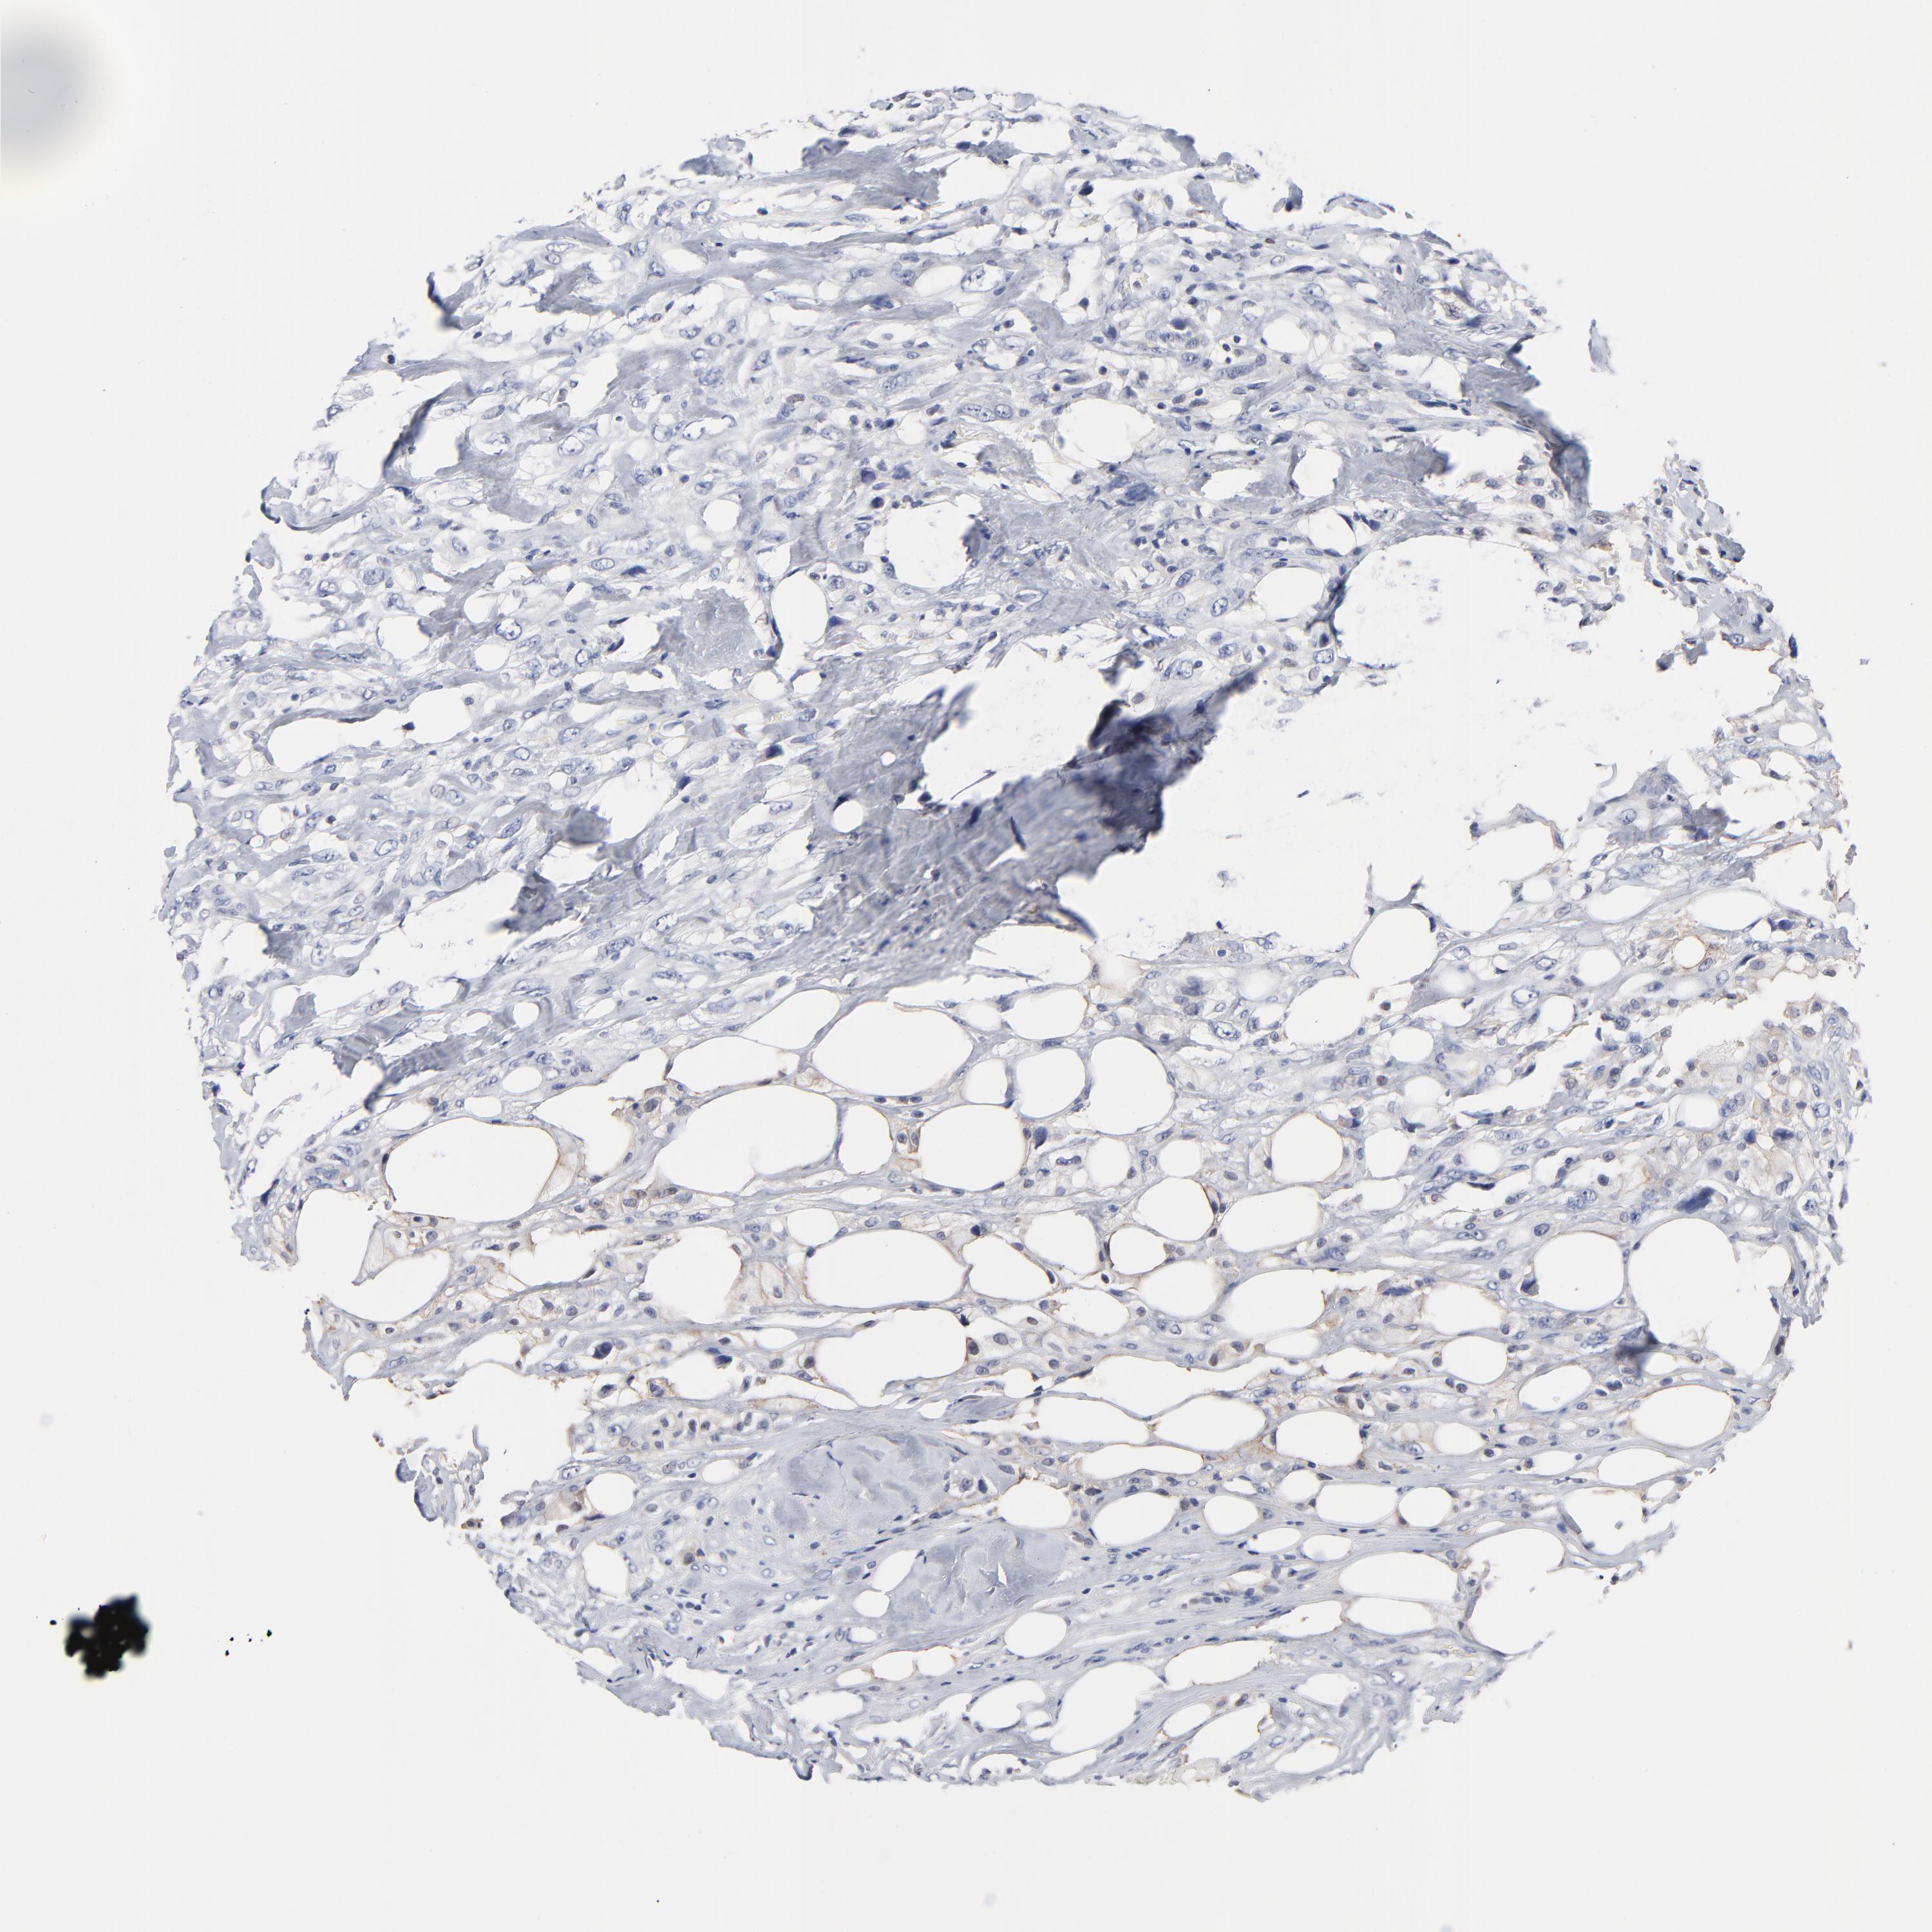

CANCER BREAST CANCER Show tissue menu

BRCA TCGA BRCA VALIDATION PROTEIN EXPRESSION